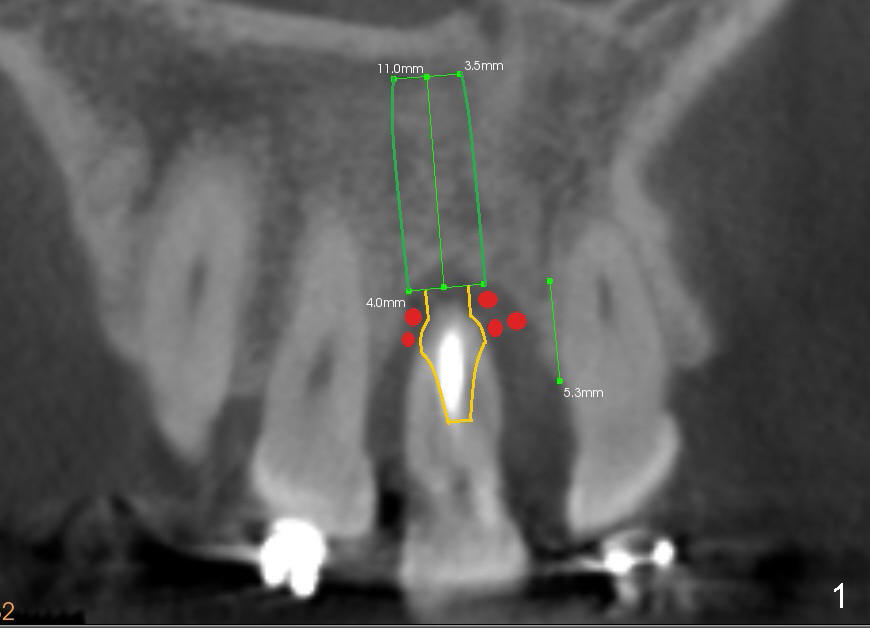

The tooth #8 of a 46-year-old lady has an endo-perio disease, complicated by occlusal trauma (Fig.1 (sagittal), 2 (coronal) CT sections).

A 4x11 mm Bicon implant with 2.5 mm well is placed, followed by insertion of a 4x6.5 mm non-shouldered abutment 15° angulation (brown outline in Fig.1).  An immediate provisional is fabricated using a 4x6.5 mm plastic sleeve, crown form and jet.

Place bone graft around the most coronal portion of the implant and apical to the hemisphere of the abutment (red circles in Fig.1).  If the labial gingiva is insufficient, harvest connective tissue graft from the palate.